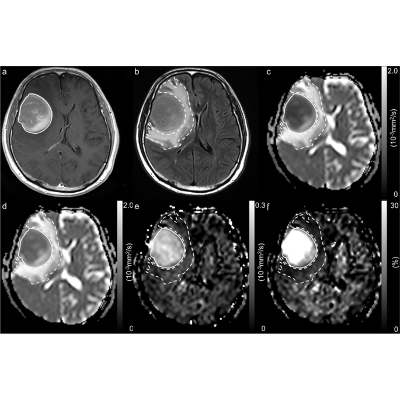

Primary diffuse large B-cell lymphoma (DLBCL) of the central nervous system (CNS) is a rare and aggressive disease, recently acknowledged as a distinct entity by the 2017 World Health Organization classification of hematopoietic and lymphoid tumors. Management of patients with newly diagnosed PCNSL is complex and requires a multidisciplinary approach....